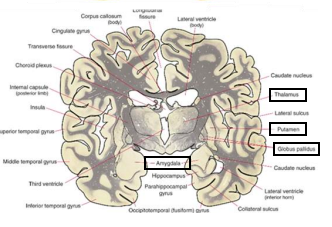

Huntington’s Disease

Loss of volume of Caudate Nucleo, enlargement of frontal horns

Enlargement of subarachnoid space, frontal convexity, interhemispheric scissure, sylvian region, and choroid fissures